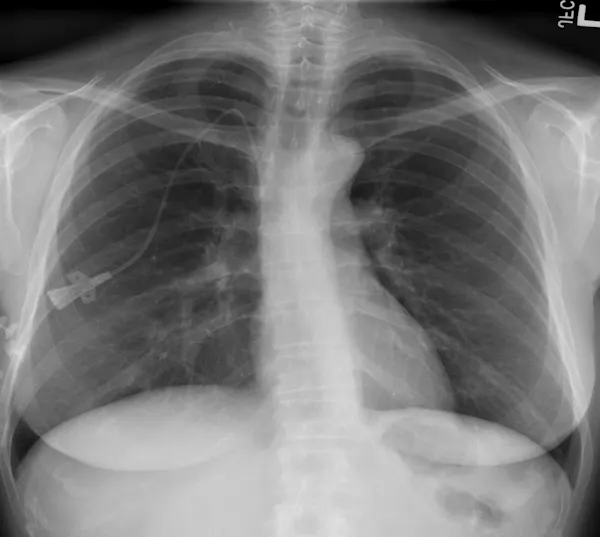

Se recurre a esta técnica de imagen porque, debido a la afectación primaria del sistema respiratorio, la infección por SARS-CoV-2 deja evidencias radiológicas de neumonía visibles bajo los rayos X. Concretamente, la neumonía asociada a la covid-19 produce sombras en los pulmones conocidas como opacidad de vidrio esmerilado. Estas opacidades suelen aparecer con una distribución periférica o posterior, principalmente en los lóbulos inferiores y con menos frecuencia en el lóbulo medio derecho.

En los dos primeros días de la infección, el 50% de los pacientes de covid-19 ya muestra lesiones pulmonares parenquimatosas, superando el 90% entre los 3 y 5 días. Lo sorprendente es que esto ocurre incluso en pacientes asintomáticos. Por ello, complementar la RT-PCR con una radiografía de tórax mejora la sensibilidad en el diagnóstico, reduciendo significativamente el número de falsos negativos. Es importante porque los falsos negativos son precisamente el talón de Aquiles de la prueba RT-PCR, cuya sensibilidad oscila entre el 70-90%. Otra ventaja importante es que la radiografía está lista en cuestión de minutos.